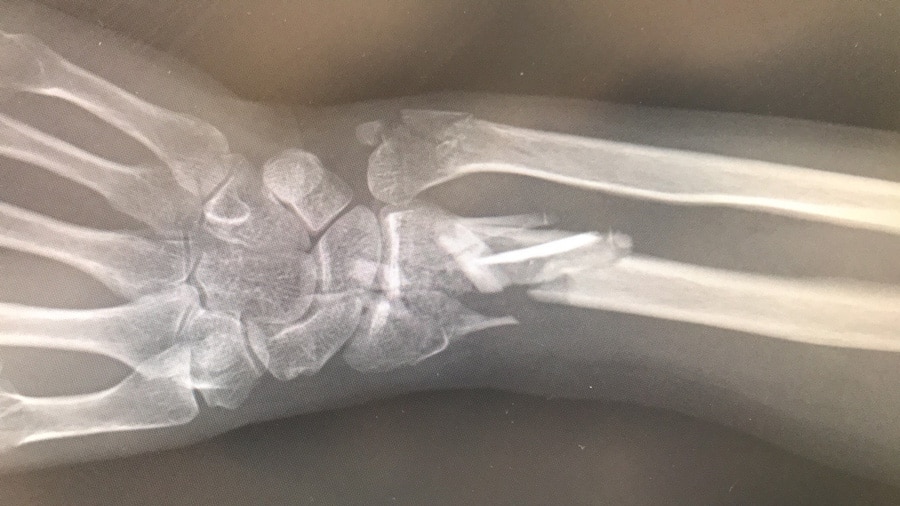

在绝经后女性中,四种类型的骨折特别常见:脊柱,臀部,近端肱骨(上臂)和远端半径(下臂)。通常,发生的第一种类型是远端径向骨折(DRF)。患有DRF的患者往往比其他类型的骨折更年轻,并且有可能随着年龄的增长而遭受更多破碎的骨骼。

远端径向骨折的原因

藤田博士及其同事发现,对肌肉弱点,平衡障碍受损与DRF之间的联系几乎没有考虑过研究。信息的稀缺性促使团队调查DRF患者的一些身体特征。他们首先确定了一组128名患有DRF作为其主要(第一)骨折的妇女,并且在手术上被治疗。将这些患者与未经历过骨折的类似年龄的128名妇女进行比较。为了确保这项研究是公平的,藤田博士和他的同事们审查了两组在更年期,手势主导和生活方式的年龄之间没有显着差异,包括患者是否吸食或喝酒等因素。